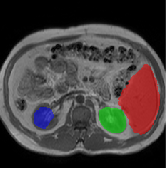

Table 2 presents an ablation study and compares SparseMamba-PCL with nine SOTA scribble-supervised methods across the three datasets. Out method achieves the highest Dice score across all the datasets, and the lowest (CHAOS) and second lowest (ACDC and MSCMRSeg) HD95 values, confirming its effectiveness in segmentation accuracy and boundary refinement. Baseline+SPOBE and Baseline+PCL improve upon the Baseline (SparseMamba), demonstrating the benefits of boundary-aware supervision and SAM-guided learning. Fig. 4 (l) compares the segmentation performance of SparseMamba-PCL with other scribble-supervised methods, showing smoother edges that precisely delineate object boundaries, unlike the jagged or blurred edges in other methods. The examples also demonstrate the consistent segmentation quality achieved by SparseMamba-PCL across ACDC, CHAOS, and MSCMRSeg, highlighting its adaptability across multiple medical domains. This adaptability and precise segmentation is crucial for accurate volumetric analysis and clinical decision-making, where even subtle boundary inaccuracies can lead to diagnostic errors. In summary, the SparseMamba-PCL architecture provides a consistent and robust improvement in segmentation metrics across diverse medical image datasets.

Refer to caption Refer to caption Refer to caption Refer to caption Refer to caption Refer to caption Refer to caption Refer to caption Refer to caption Refer to caption Refer to caption Refer to caption

(a) (b) (c) (d) (e) (f) (g) (h) (i) (j) (k) (l)

Figure 4: Qualitative comparison of weakly-supervised segmentation methods on ACDC, CHAOS, and MSCMRSeg datasets. (a) Input image, (b) ground truth, and segmentation results from (c) USTM [16], (d) Scribble2D5 [5], (e) CycleMix [26], (f) ShapePU [27], (g) S²ME [21], (h) ScribbleVC [12], (i) TDNet [30], (j) PacingPseudo [25], (k) Scribbleformer [13], and (l) SparseMamba-PCL are given.